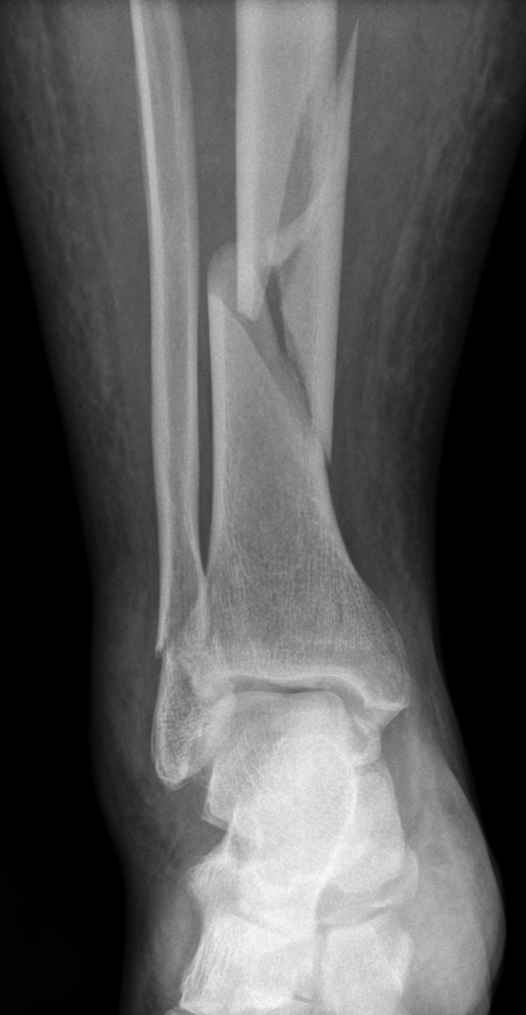

Röntgenaufnahme des Unterschenkels bei komplexer Fraktur von Scheinbein und Wadenbein.